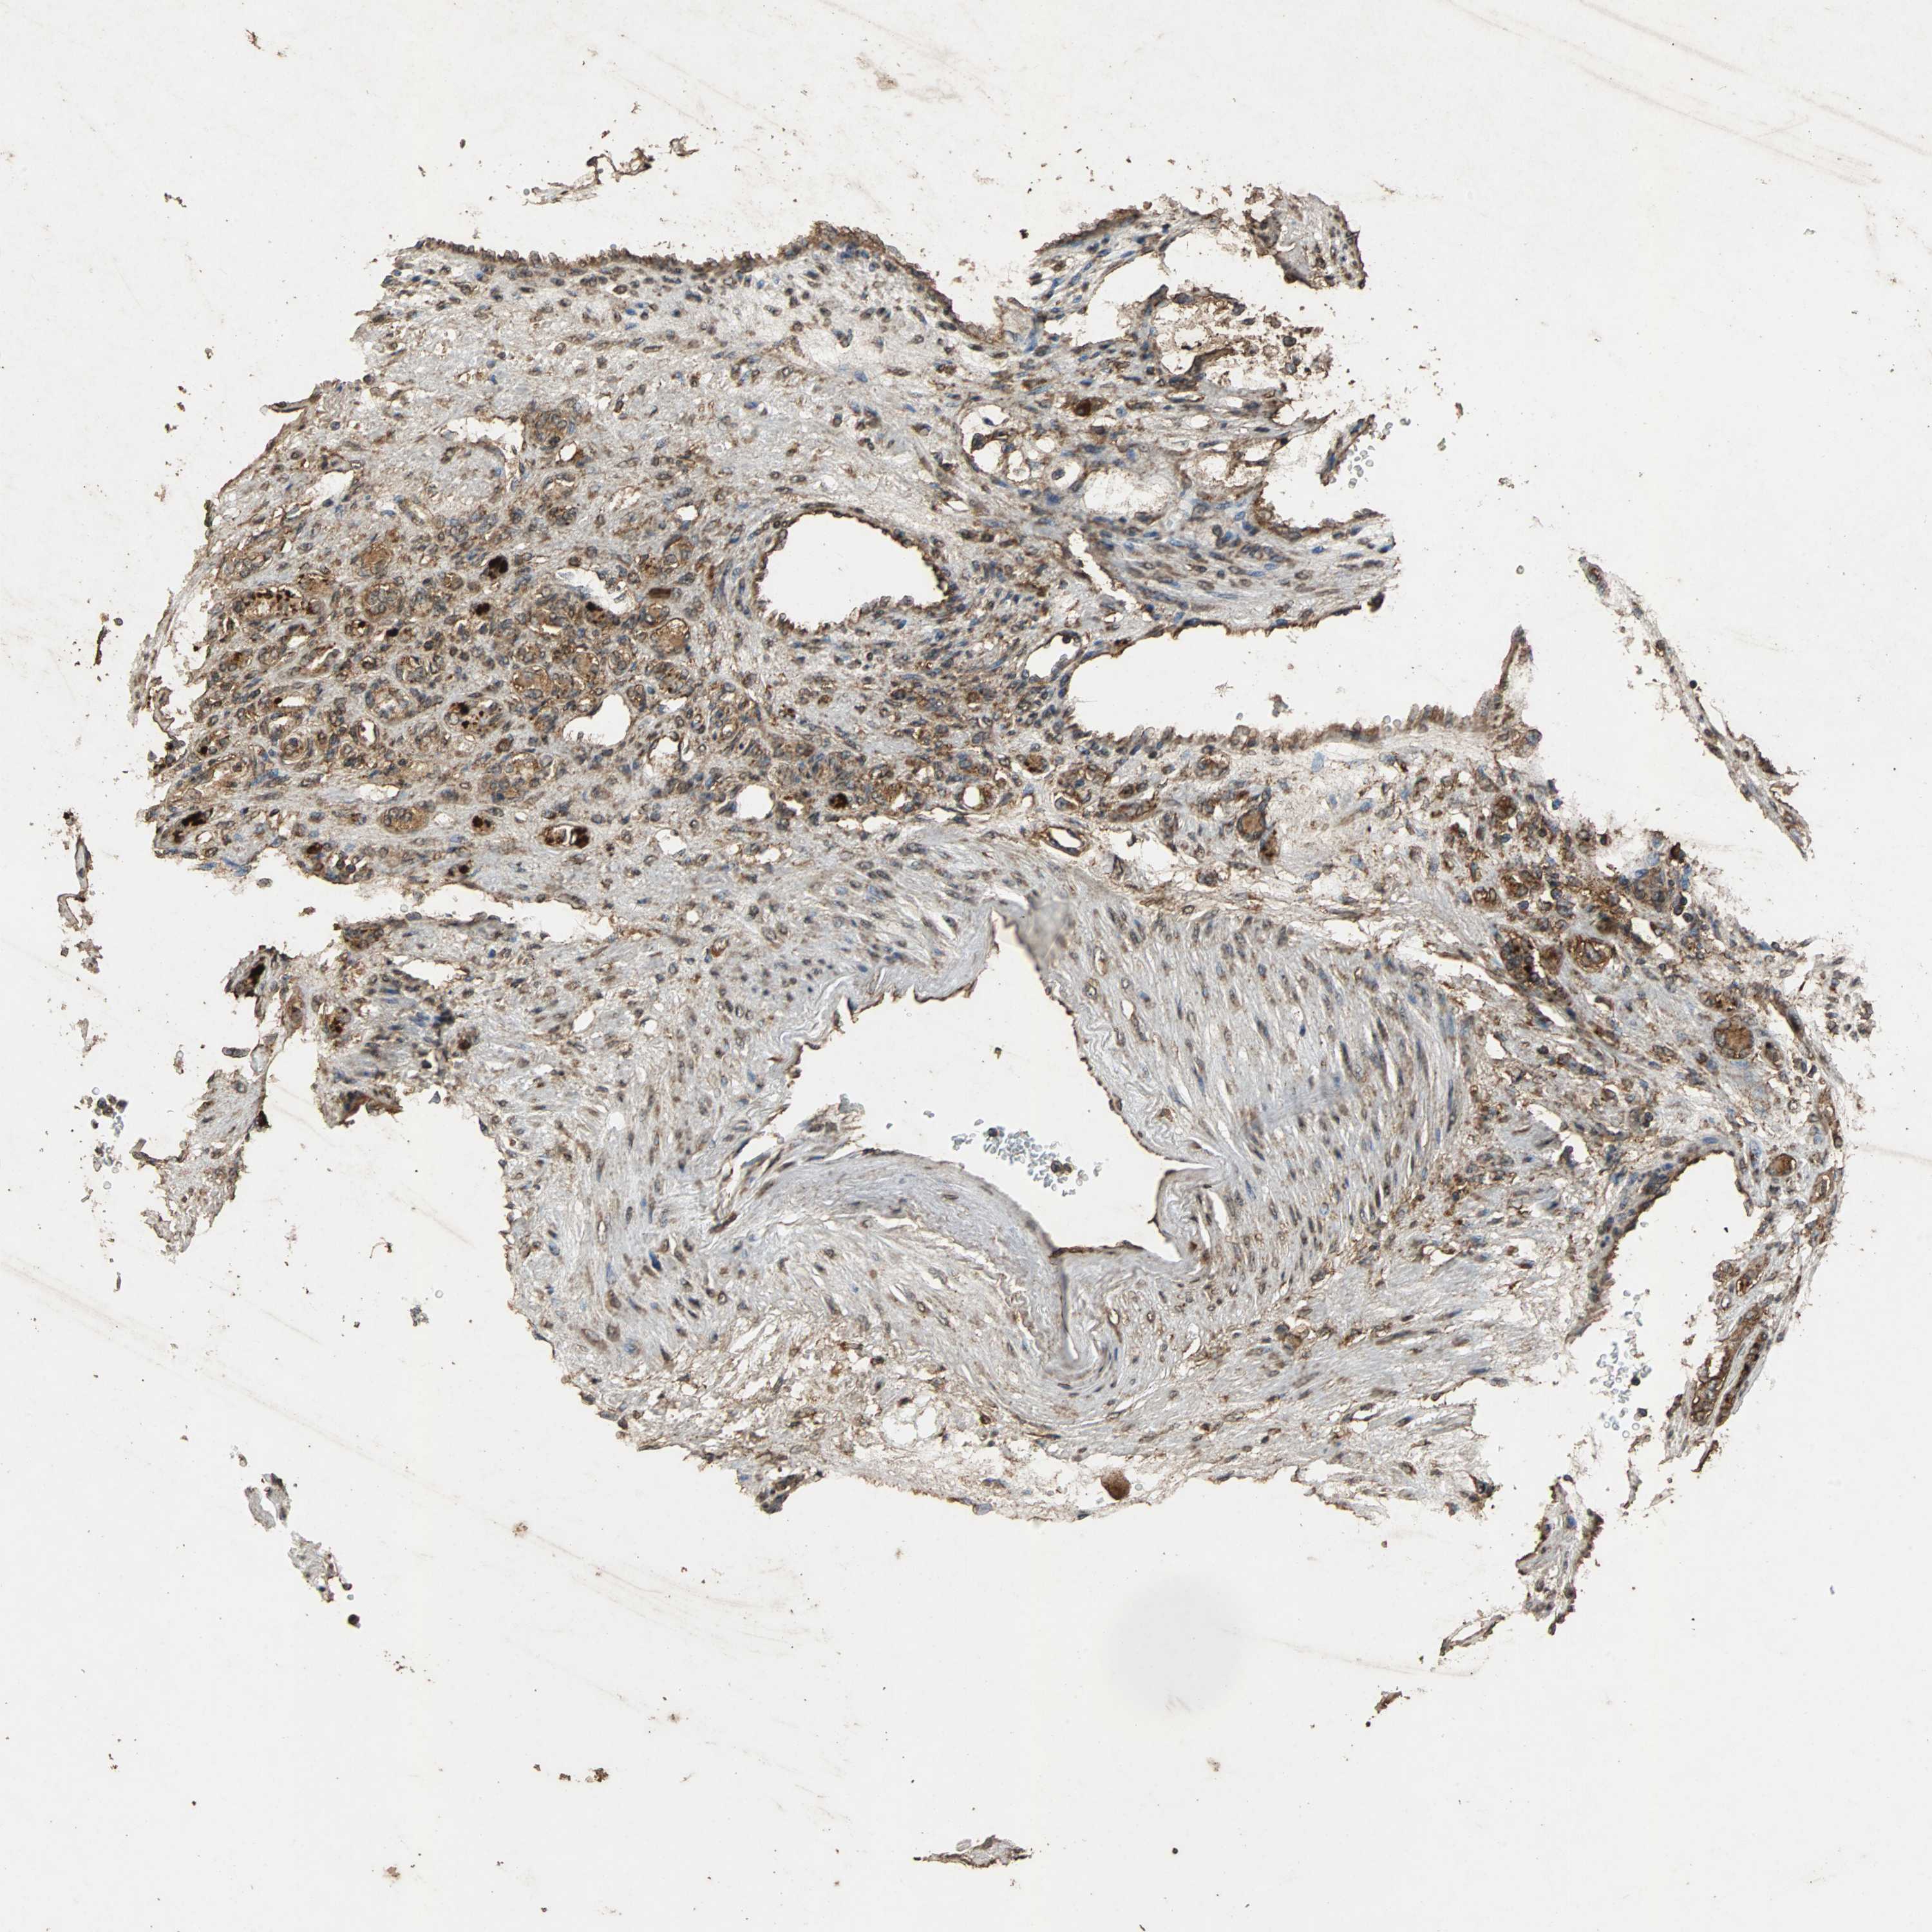

TCGA RNA samplesi

RNA-seq data is reported as average FPKM (number Fragments Per Kilobase of exon per Million reads), generated by the The Cancer Genome Atlas (TCGA) .

Normal distribution across the dataset is visualized with box plots, shown as median and 25th and 75th percentiles. Points are displayed as outliers if they are above or below 1.5 times the interquartile range. FPKM values of the individual samples are presented next to the box plot.

Average pTPM 24.6

Number of samples 100